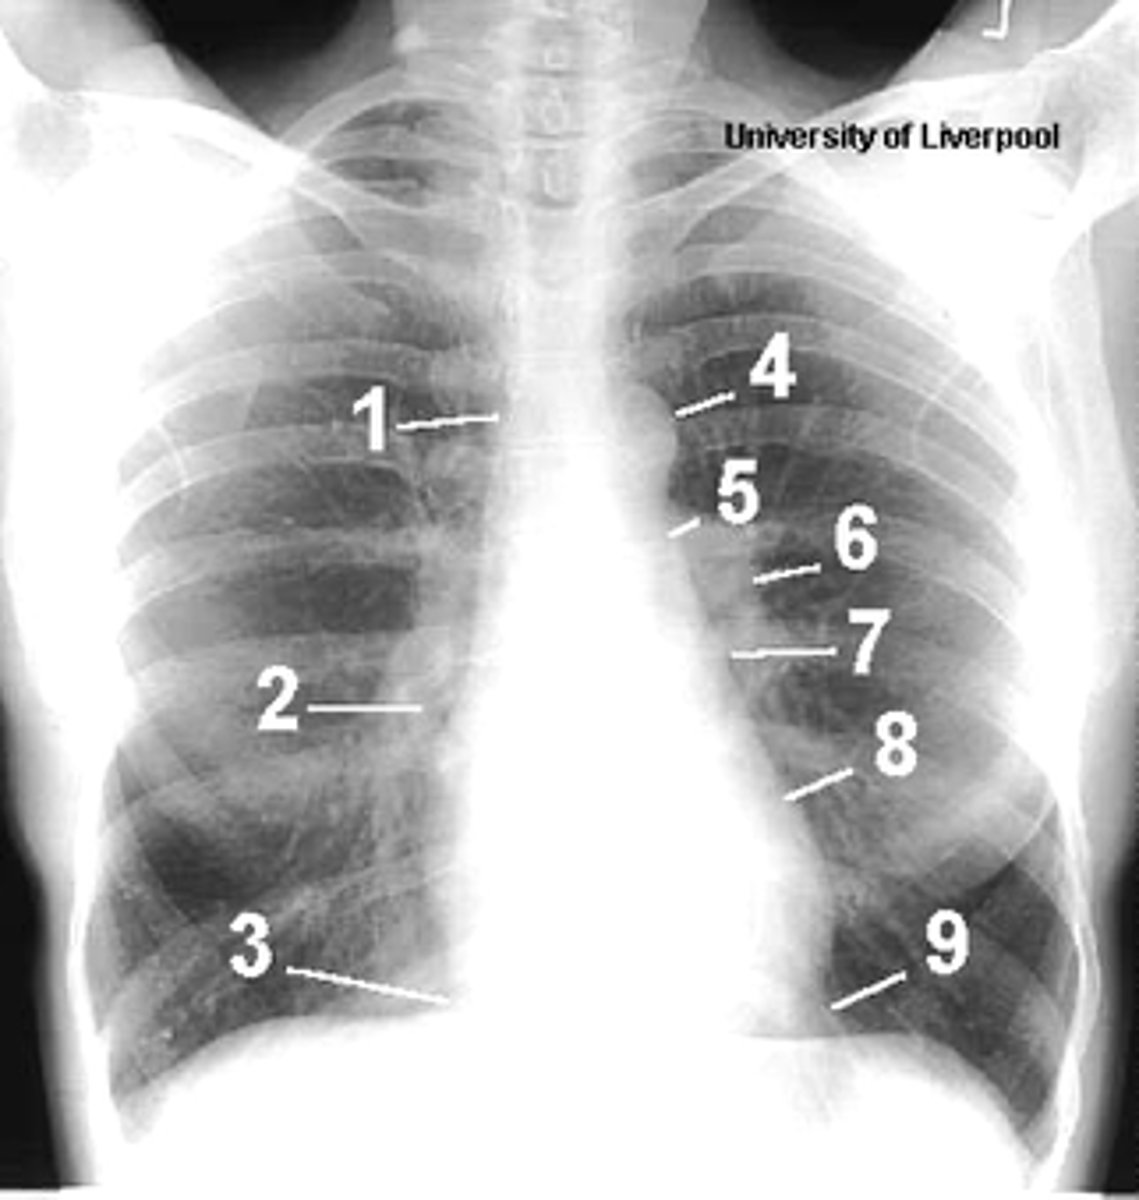

1

superior vena cava

2

right atrium

3

inferior vena cava

4

aortic arch or knob

5

left pulmonary trunk

6

left pulmonary artery

7

left atrium

8

left ventricle

9

left cardiophrenic angle